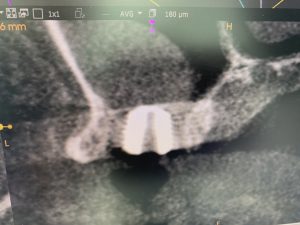

新大久保歯科医院にて朝イチから、残存骨1〜2ミリのソケットリフトオペあり。

今朝は暖かいなぁ〜春近し! 抜歯後2ヶ月経過

洞内には、人工骨は一切使わず、採血し遠心分離器により得られたCGFメンブレンとバーにより飛散された自家骨のみ! 結果はグー!ね

切開から埋入まで25分で終了 やはりこの手法は非常に良い!

自信から確信に変わったよ! 第五世代の治療と、カリスマ先生がネーミングされてます